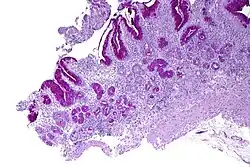

Micrograph showing nodular enterochromaffin-like cell hyperplasia, as demonstrated with chromogranin A immunostaining, in the body of the stomach. Parietal cells are not readily apparent. These changes are in keeping with autoimmune metaplastic atrophic gastritis, a histologic correlate of vitamin B12 deficiency anemia.

PA may be considered as an end stage of autoimmune atrophic gastritis, a disease characterised by stomach atrophy and the presence of antibodies to parietal cells and intrinsic factor.[38][39] Autoimmune atrophic gastritis, is localised to the body of the stomach, where parietal cells are located.[36] Antibodies to intrinsic factor and parietal cells cause the destruction of the oxyntic gastric mucosa, in which the parietal cells are located, leading to the subsequent loss of intrinsic factor synthesis. Without intrinsic factor, the ileum can no longer absorb the B12.[40] Atrophic gastritis is often a precursor to gastric cancer.[39]